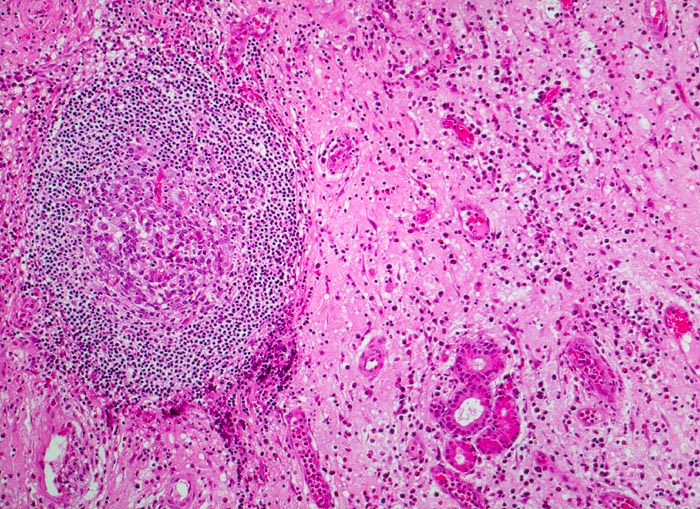

chronische polypöse Rhinitis

Nasenschleimhaut

Vermehrtes ödematöses Stroma mit spindeligen Fibrozyten und gemischtem Entzündungsinfiltrat. Lymphfollikel mit Keimzentrum. Blutgefässe gefüllt mit Erythrozyten und Entzündungszellen. Seromuköse Drüse der Nasenschleimhaut.

Patient mit nicht allergischem Asthma klagt über chronische dumpfe Kopfschmerzen und behinderte Nasenatmung. Bei der anterioren Rhinoskopie sind multiple Polypen der Nasenschleimhaut im Bereich des mittleren Meatus sichtbar.